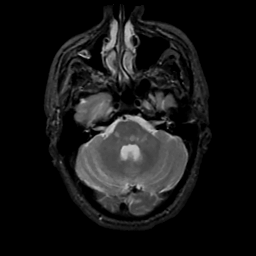

MR Study #1, February 10, 1991 -- Slice #12